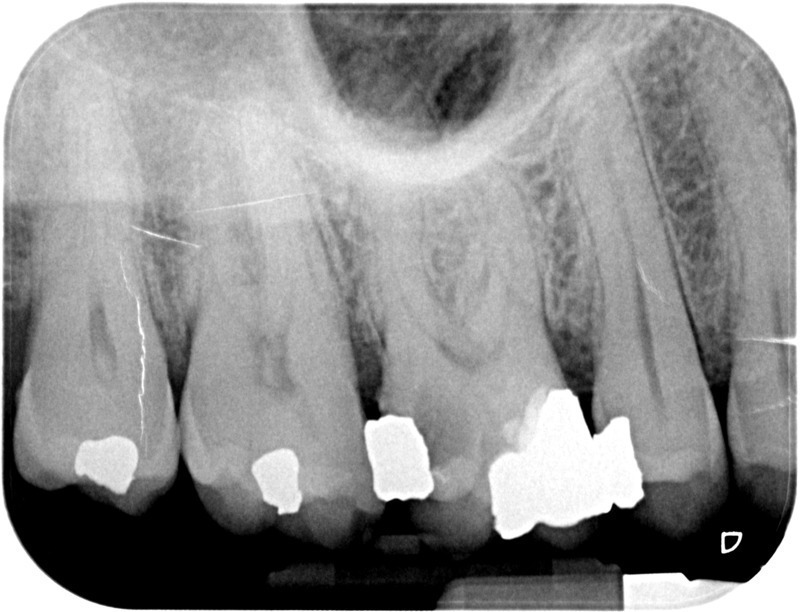

• Reprise de traitement endodontique : La manœuvre consiste à retourner à l’intérieur des racines d’une dent déjà traitée. Il arrive occasionnellement qu’une nouvelle inflammation se déclare suite à une reprise de carie ou une fracture de la dent, ou si le premier traitement endodontique est incomplet. Après s’être assuré que la dent lésée était conservable, il convient de désinfecter de nouveau le réseau canalaire parfois très complexe. La nouvelle obturation des canaux devra être protégée aussi rapidement que possible pour éviter une éventuelle contamination bactérienne.

Après